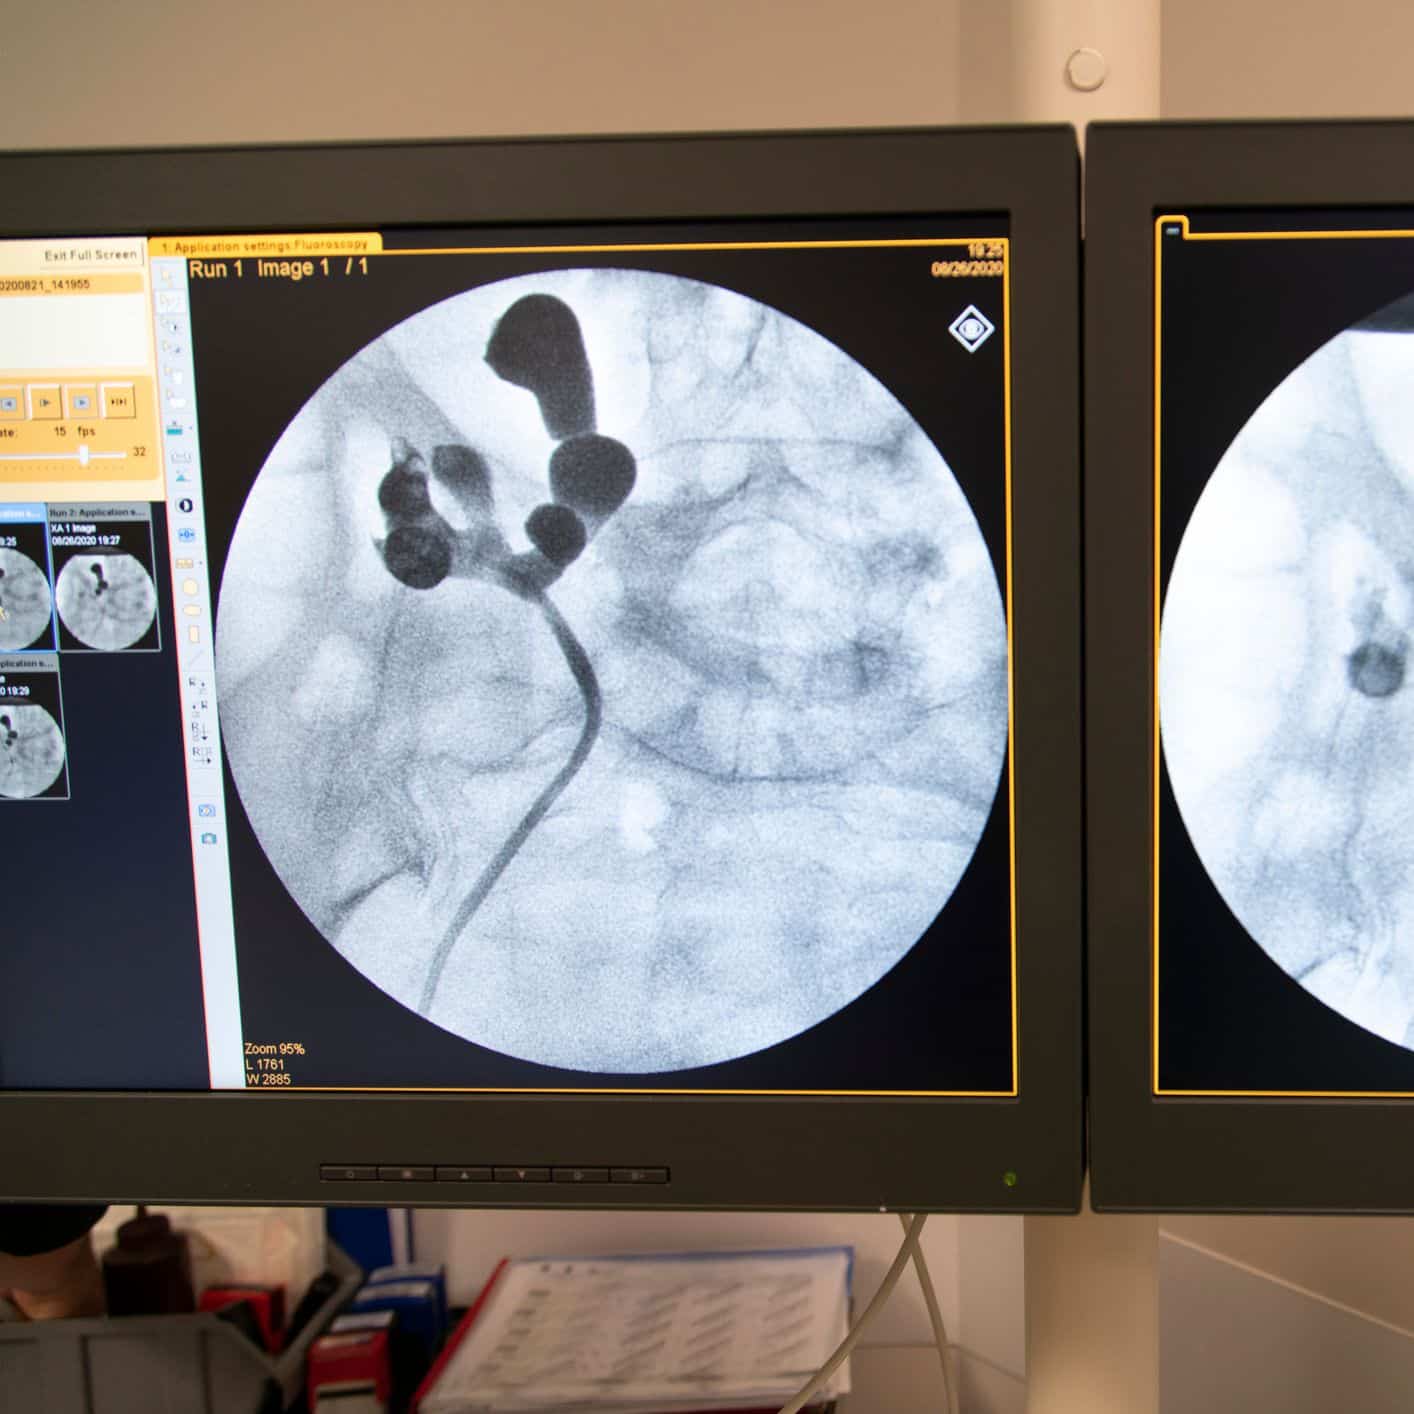

Cuídate con Radio 5 Cuídate con Radio 5 – Piedras en el riñón y en la vesícula –

Los cálculos renales y vesiculares centran la consulta de este lunes con la Doctora Internista Carmen Díaz Pedroche. Además, hablamos con, Arturo Fraga Bau, neurólogo en el Complejo Hospitalario Universitario de Vigo sobre la campaña de concienciación puesta en marcha por la Fundación Atrofia Muscular Espinal, que cuenta con la música como hilo conductor.